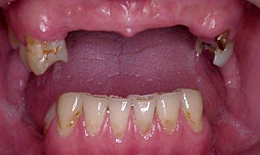

インプラント症例(1)30代 女性

治療前

上顎

保存困難な歯を抜歯後、インプラントを7本埋め込み、セラミックスクラウンを被せた

下顎

保存困難な歯を抜歯後、インプラントを6本埋め込み、セラミックスクラウンを被せた